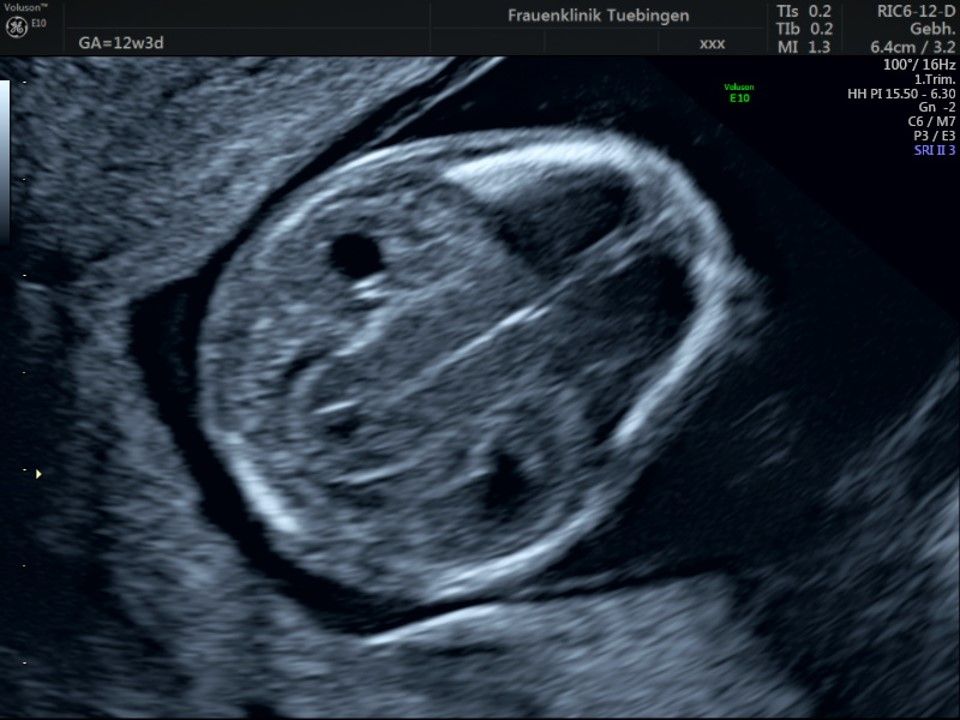

Im Rahmen des Ersttrimester-Screenings untersuchen wir die Organe des Feten mittels Ultraschall. Dabei machen wir auch gerne ein Bild für Sie.

Obwohl der Fet zu diesem Zeitpunkt erst zwischen 5 und 8cm groß ist, lassen sich bereits etwa die Hälfte aller schwerwiegenden Fehlbildungen erkennen bzw. ausschließen. Sollten wir eine Auffälligkeit sehen, werden wir mit Ihnen den Befund und das weitere Vorgehen ausführlich besprechen.

Die eigentliche Organuntersuchung findet um die 20.SSW (zweites Screening) statt. Das Ersttrimester-Screening und das zweite Screening sind sich ergänzende Untersuchungen und ersetzen sich gegenseitig nicht.

Fetale Anatomie